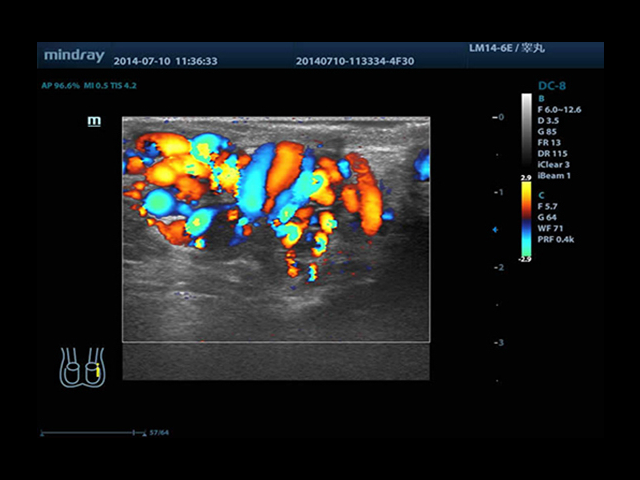

Mindray DC-8 Exp оснащен новым поколением датчиков с увеличенным количеством элементов и инновационной технологией "3T". Это позволяет достичь высокой детализации и качества изображения. Благодаря новейшей технологии iFlow, можно визуализировать даже самые мелкие сосуды и кровеносные пути.

Сверхширокополосная нелинейная обработка изображений снижает визуальные шумы на 30% по сравнению с другими системами. Технология iClear позволяет устранить зернистость изображения, а iBeam (технология пространственного компаундинга) обеспечивает высокое качество сканирования органов и тканей под различными углами.

• HR-flow™ - режим отображения кровотока с высоким временным и пространственным разрешением для точной и однородной визуализации сосудов, в том числе самых мелких

• Natural Touch Elastography - опция оценки эластичности ткани (эластография), с программой анализа. Действует на линейных и внутриполостных датчиках. Компрессионный метод.